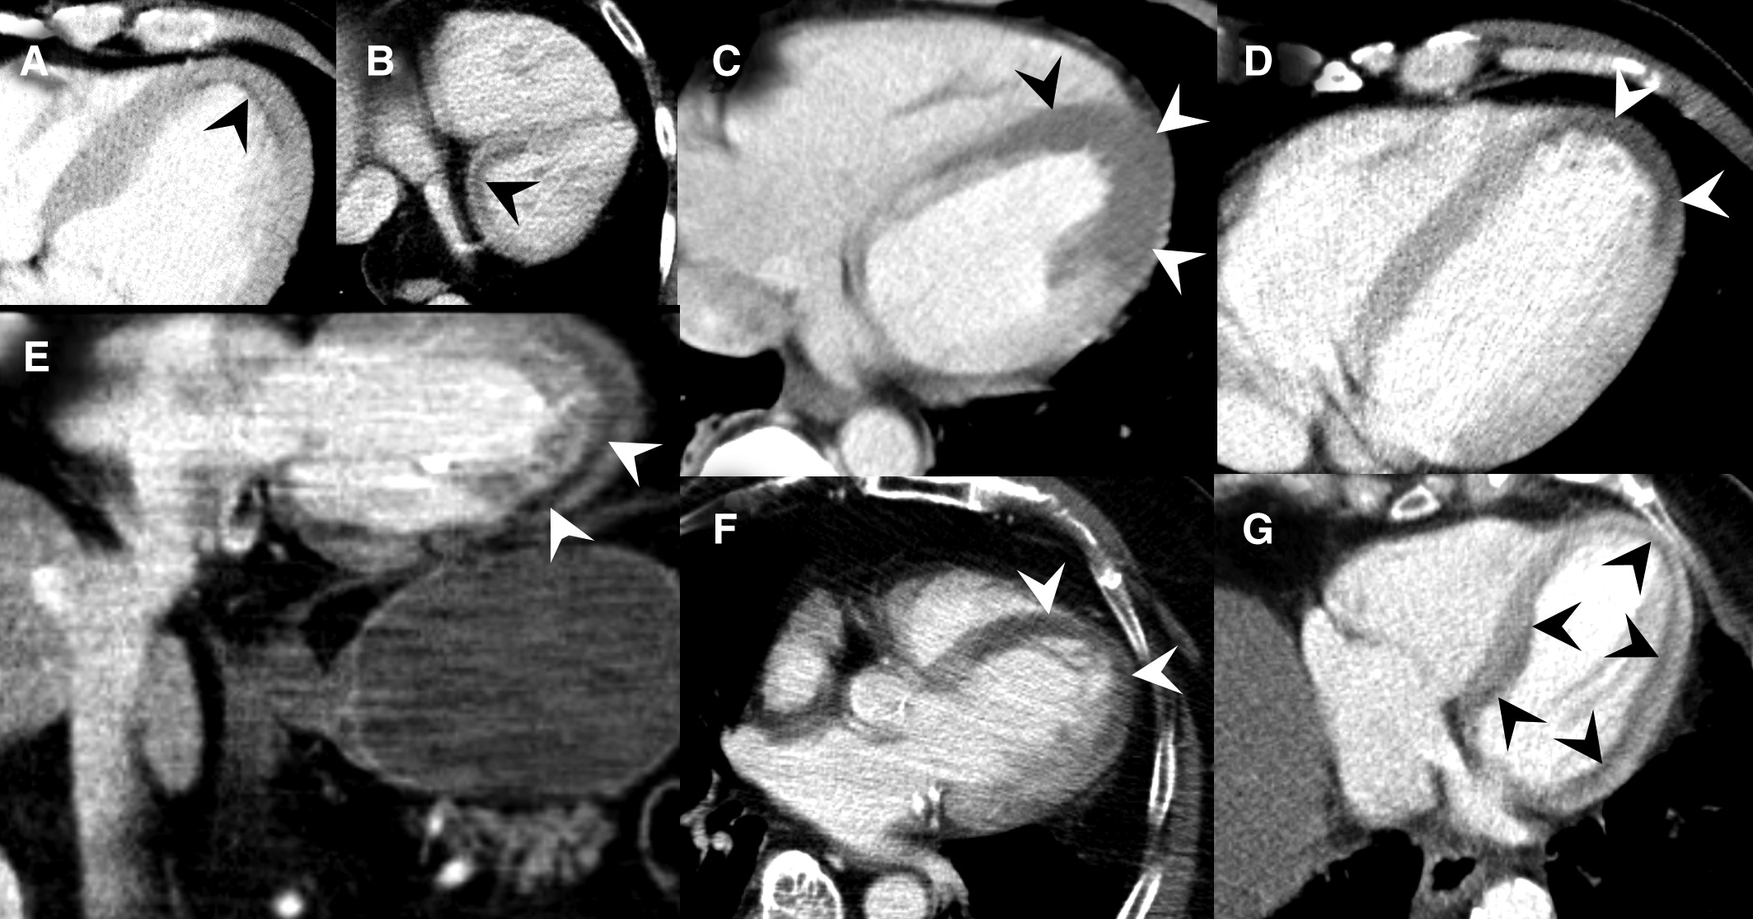

Figure 7

Collection of MDCT images of patients with MH (black and white arrowheads) caused by acute MI. (A) Slight subendocardial perfusion deficit at the heart apex. (B) Coronal slice through the heart base showing predominately subendocardial MH. (C) Extensive MH at the left ventricle. (D) Coronal reformats with impressive MH at the cardiac apex. (E) Axial MDCT slices demonstrating MH at the cardiac apex. (F) Subendocardial MH along the entire left ventricle.